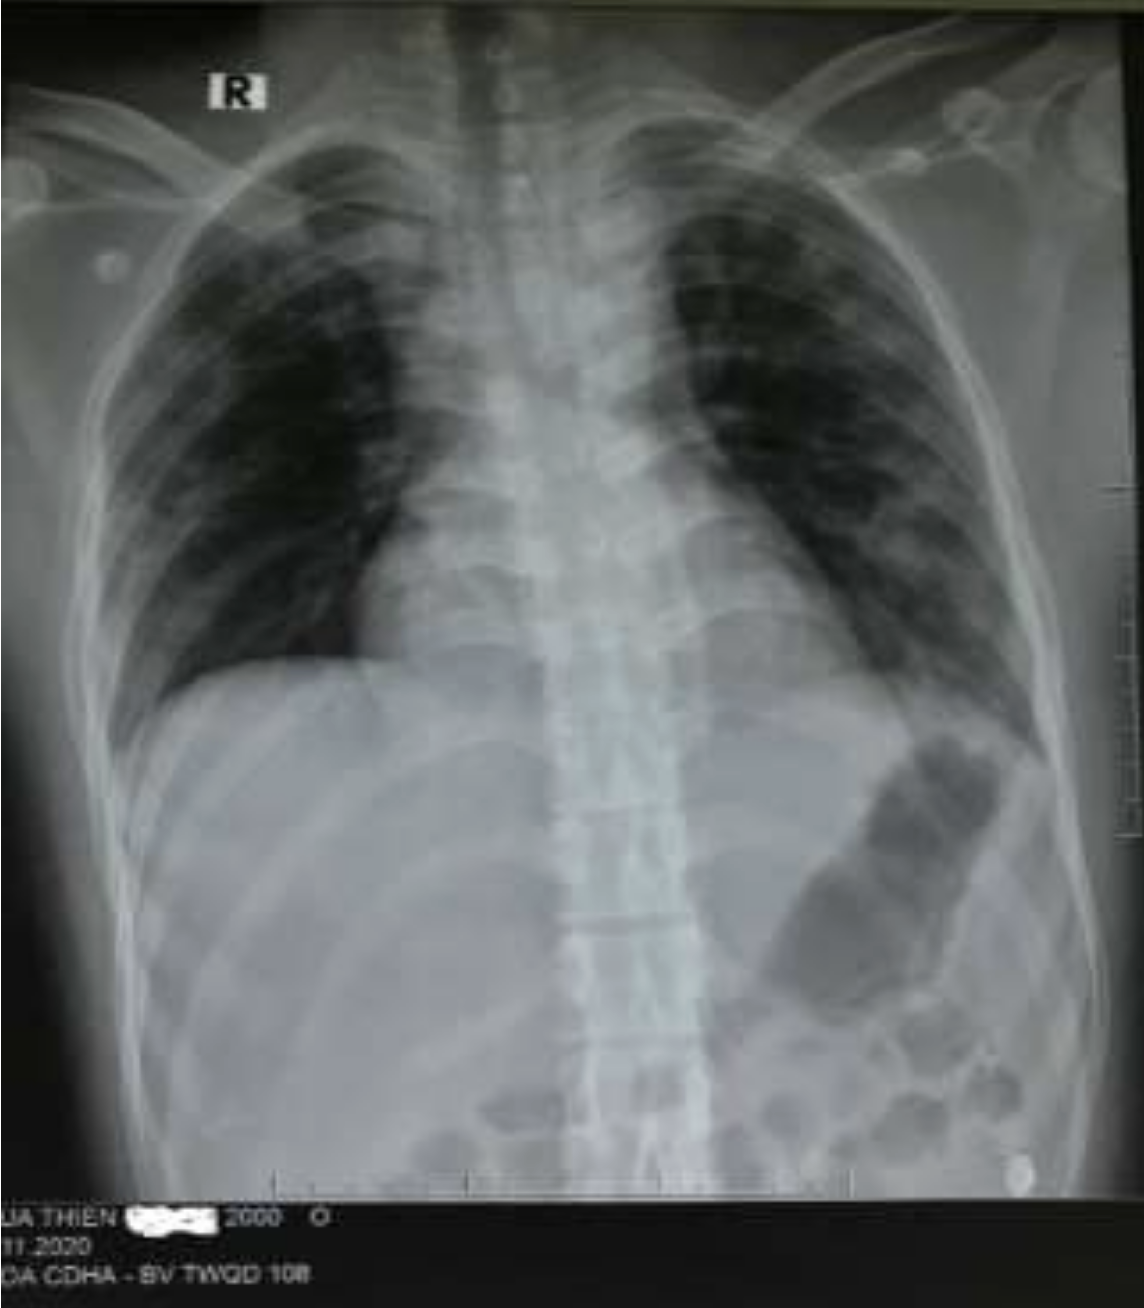

Hình ảnh X-quang ngực thẳng: Mờ lan tỏa 2 phế trường.

Kết quả điều trị, bệnh nhân rút ống nội khí quản sau 3 ngày, hình ảnh tổn thương trên X-quang và tình trạng hô hấp hồi phục gần như hoàn toàn.